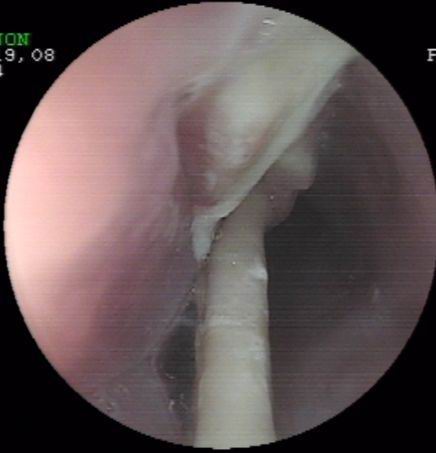

上個月末,一誤食異物(雞骨)胸骨后疼痛4天的患者經(jīng)胃鏡檢查確診為食管異物嵌頓。因患者異物嵌頓時間長,且患者其間還采取了其它一些清除異物的方法,造成異物的兩端均刺入食管壁,刺入處食管粘膜糜爛,充血,腫脹。按常規(guī),該患者應(yīng)收治外科行開胸手術(shù)取出術(shù),但患者家境貧寒,且為家里主要勞力,無法承受醫(yī)療費(fèi)用及開胸術(shù)后所造成暫時的勞動能力降低的損失。為減輕患者經(jīng)濟(jì)負(fù)擔(dān)及痛苦,在確診食管異物尚未造成食管周圍重要臟器損傷的情況下,該室決定在胃鏡下試取,經(jīng)多方面嘗試,最終成功將一長約3.6cm兩端鋒利的雞骨(圖示)行內(nèi)鏡下取出,術(shù)后患者康復(fù)好,真正做到了微創(chuàng)手術(shù)解除患者大問題,減輕了患者經(jīng)濟(jì)及軀體負(fù)擔(dān)。